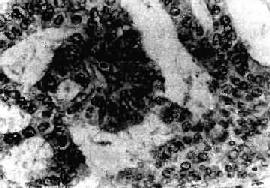

图13-8 子宫体腺癌(弥漫型) 癌组织弥漫浸润子宫壁,且部分突入子宫腔中形成大不不等的乳头状肿块 镜下,子宫内膜癌多数为分化较好的腺癌。腺体数目增多,形状和大小不一,排列紊乱,腺体呈“背靠背”形式。腺体由单层或复层细胞组成,形成条索状“搭桥”。间质极少。有时腺上皮增生形成实体性癌巢。癌细胞呈柱状或多角形,可有不同程度的分化。胞浆中等量,淡染;核大小不一,染色质增多而深染,核仁明显,可有正常或病理核分裂像。根据分化程度,子宫内膜癌可分为3级:Ⅰ级(高分化腺癌),腺体较规则,同单层细胞组成,细胞排列紧密有的成假复层或复层。核分裂像少见(图13-9)。Ⅱ型(中分化腺癌),腺体不规则,有较多腺样结构或小腺体形成,可有少量实性区。癌细胞分化较差,核分裂像易见。Ⅲ级(低分化腺癌),腺体结构极少见,癌巢多呈实性片块状,细胞异型性明显,核分裂像多见。有些腺癌组织中可见良性化生的鳞状上皮团,称腺棘癌(adenoacanthoma)。如果腺癌内混有恶性鳞状上皮,称腺鳞癌(adenosquamous carcinoma),多见于分化较差的腺癌。少数子宫内膜癌含有透明细胞,或含粘液的细胞。有些可形成乳头状子宫内膜癌。

图13-9 子宫内膜腺癌 呈腺样结构,癌细胞呈柱状和立方形,核异型明显,排列紊乱 【扩展和转移】 一般,子宫内膜癌生长较缓慢,局限在子宫内膜的时间较长,但也有极少数发展较快者。其转移途径主要是淋巴道转移、直接蔓延,晚期也可有血行转移。 1.淋巴道转移 宫底部的癌多转移至腹主动脉旁淋巴结;癌在子宫角时可沿圆韧带的淋巴管至腹股沟淋巴结;子宫下段及扩散到宫颈管的癌灶,与宫颈癌的淋巴道转移途径相同,可至子宫旁、髂内外和髂总淋巴结。 2.直接蔓延,向上经子宫角至输卵管;向下至颈管、阴道;向外经肌层浸润至浆膜面而蔓延至输卵管、卵巢,并可广泛种植在腹膜、子宫直肠窝有大网膜等处。 3.血行转移,晚期患者可经血行转移至肺、肝有骨等处。